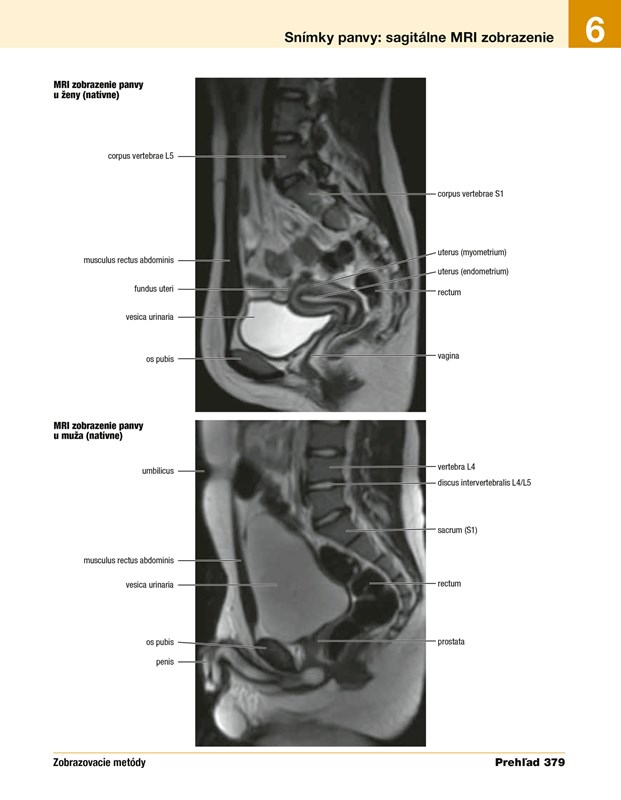

Vyše 50 rádiologických snímok, pričom niektoré sú v atlase publikované prvýkrát, niektoré predchádzajúce snímky sú nahradené novými, získanými modernejšími prístrojmi. Jednotlivé snímky boli vybrané na základe ich prínosu pre študentov.